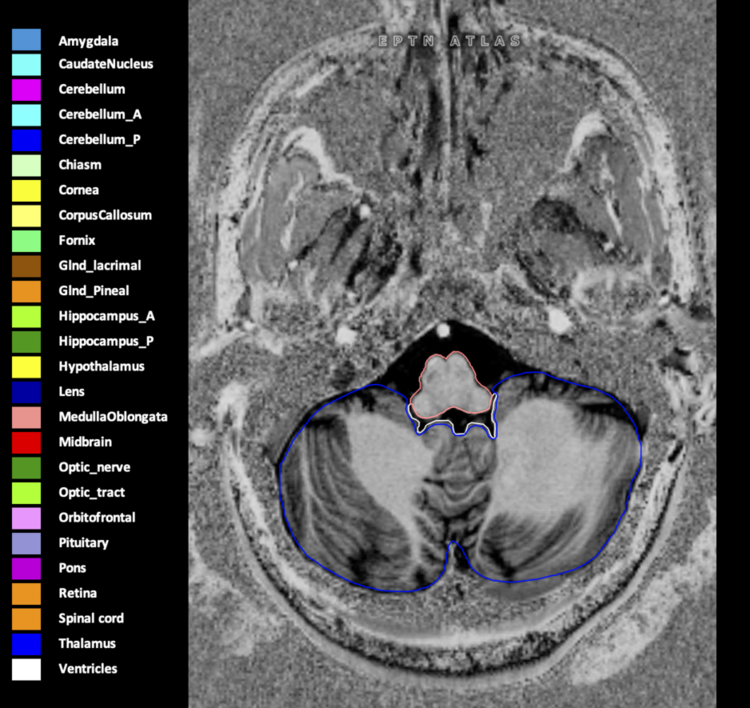

Eekers et al. have published an international neurological atlas for contouring of organs at risk in consensus with the European Particle Therapy Network (EPTN) in 2018 and an update in 2021. The purpose of this consensus atlas is to decrease inter- and intra-observer variability in delineating OARs relevant for neuro-oncology.

Included are all OARs known to be relevant for radiation-induced toxicity in neuro-oncology: brain, brainstem (midbrain, pons, medulla oblongata), chiasm, cerebellum (anterior & posterior), cochlea, cornea, hippocampus (anterior & posterior), hypothalamus, lens, lacrimal gland, optic nerve, pituitary, skin, and vestibular & semicircular canals. To further facilitate research on cognition, vision and radiological changes after irradiation of the brain, potential clinically-relevant OARs are included: amygdala, caudate nucleus, cerebellum (anterior & posterior), corpus callosum, fornix, macula, optic tract, orbitofrontal cortex, periventricular space (PVS), pineal gland, and thalamus.

We propose this atlas is used in photon and particle therapy in order to derive consistent dosimetric data. When required this atlas will be updated according to new insights.

Three-dimensional delineation of the 25 consensus OARs for neuro-oncology are shown on CT (WW/WL 120/40, 3000/600), 3T MR images, (T1Gd, T2FLAIR 1mm) and 7T MR (MP2RAGE 0.7 mm). All are presented in transversal, sagittal and coronal view.